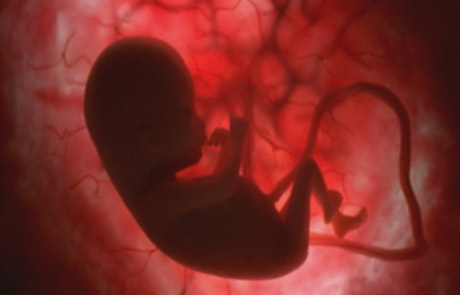

Entre el cuarto y el quinto mes se aprecia claramente la silueta y las extremidades del futuro bebé.

A las 24 semanas ya abre y cierra los ojos, saca la lengua y tiene su primer ataque de hipo

Entre el cuarto y el quinto mes se aprecia claramente la silueta y las extremidades del futuro bebé.

A las 24 semanas ya abre y cierra los ojos, saca la lengua y tiene su primer ataque de hipo